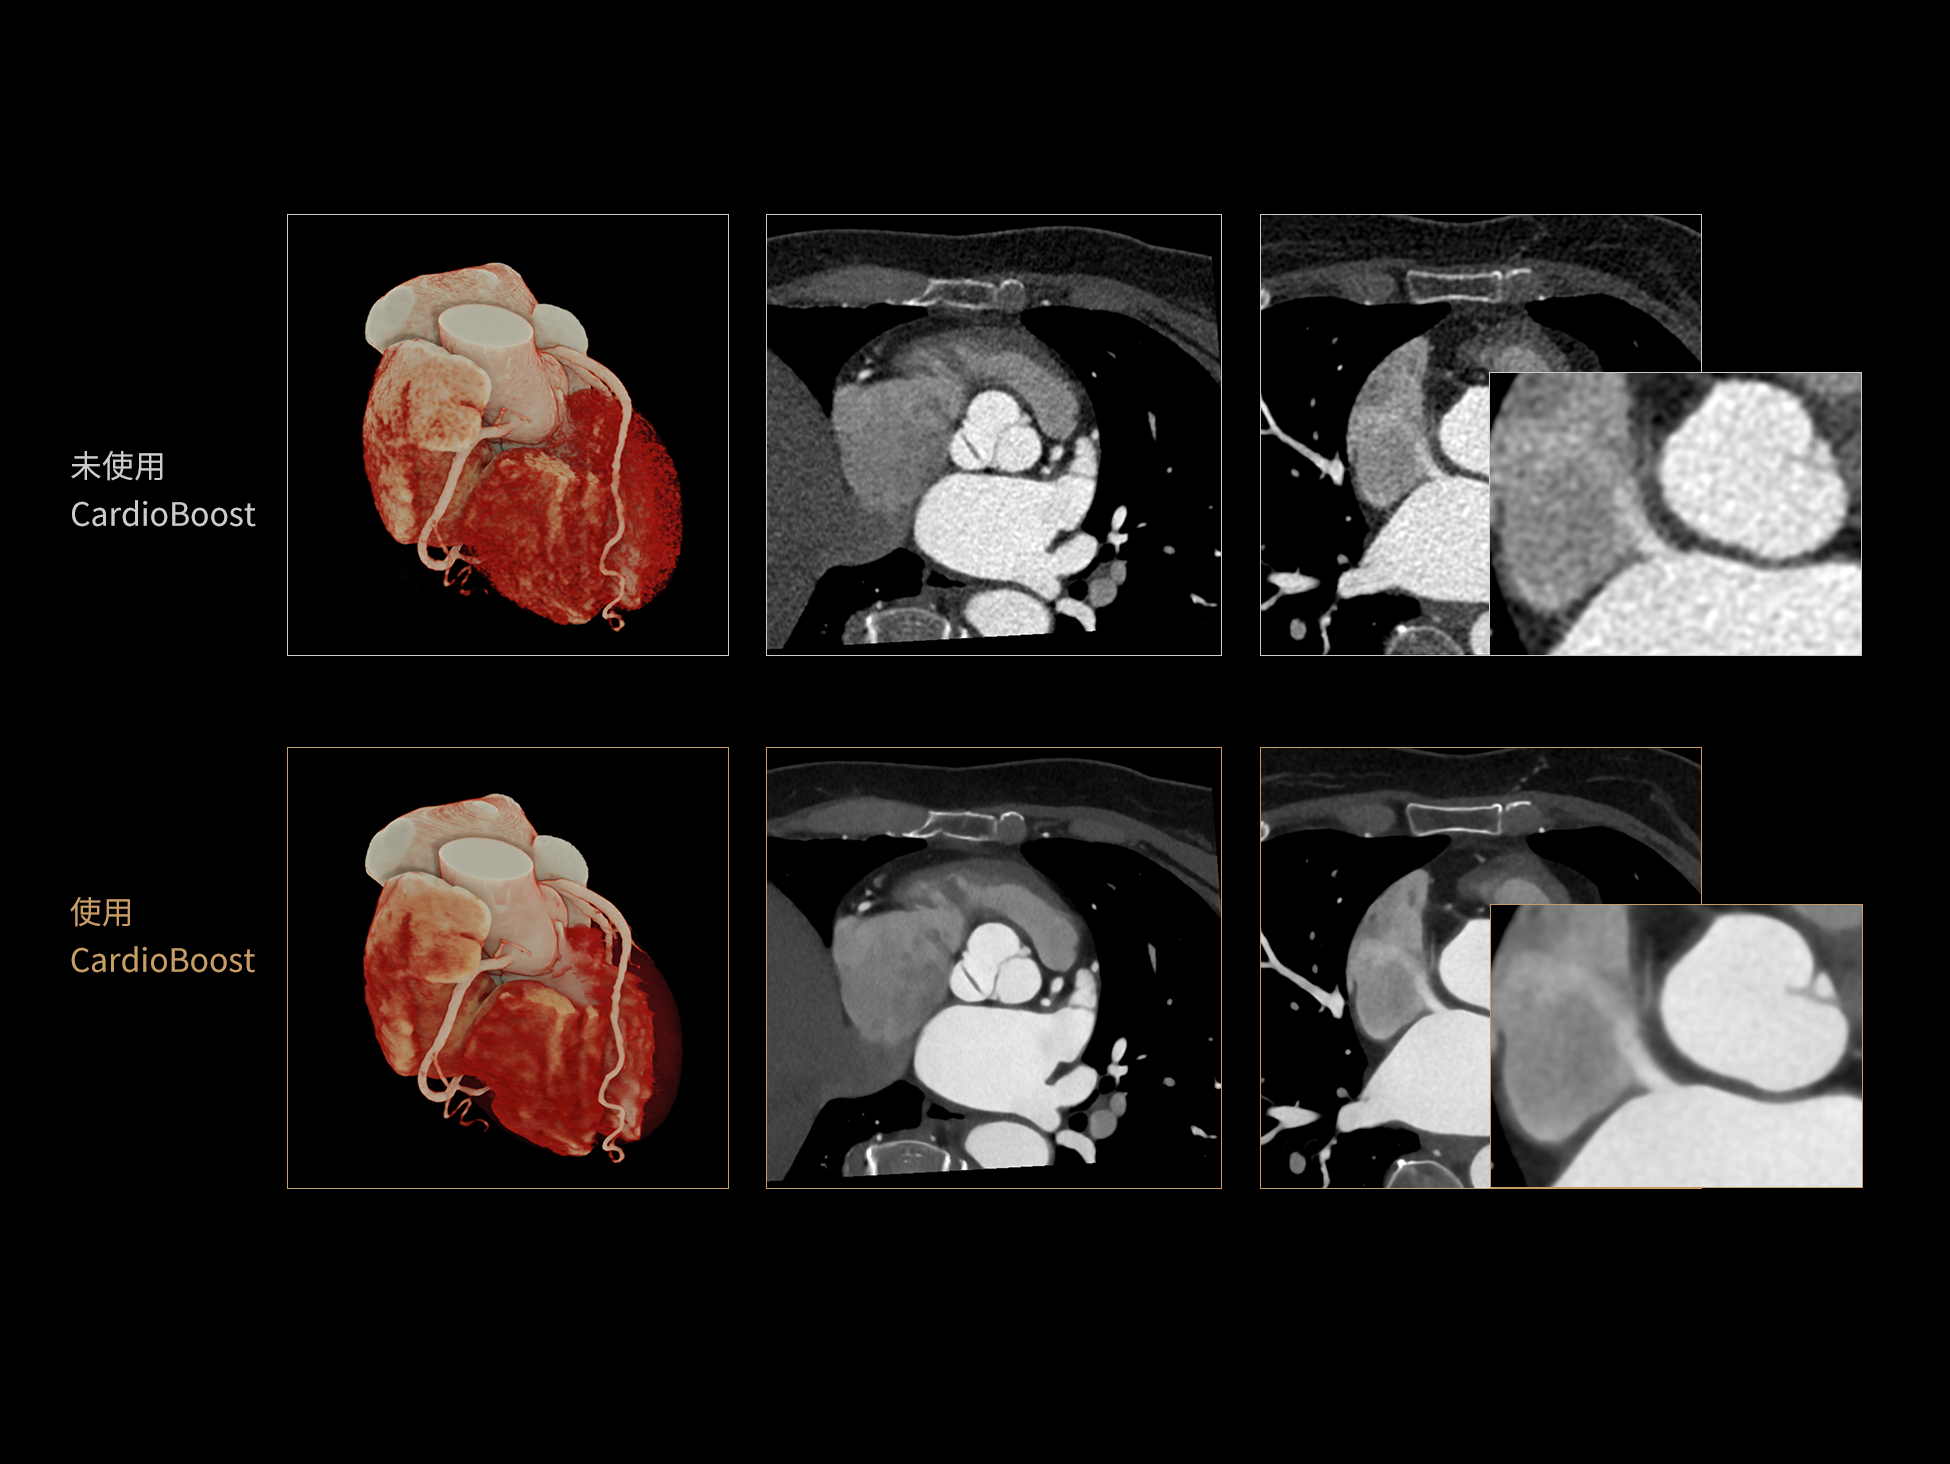

CardioBoost:专属网络设计,重塑心脏影像表现

uCT 868 搭载联影最新一代 uSense 人工智能平台,将智能化深度融入 CT 扫描全流程,从感知细微生理运动到精细结构探测,再到多场景诊疗优化。以 AI 为核心驱动力,uSense 重塑成像各环节,打造高效、高清的智慧扫查体验。在心脏成像领域,uSense 结合宽体探测器、心脏专研AI重建算法与AI冠脉运动追焦技术,在保持低剂量的同时,有效抑制运动伪影,精准呈现软斑块、混合型斑块及支架细节,助力冠脉成像惠及更多患者。针对多科室疾病临床应用场景,uSense 平台提供全方位的智能解决方案:包括头部运动伪影智能校正、金属植入物伪影抑制、扫描视野扩展等先进算法。这些创新技术使 uCT 868 能够构建覆盖全场景的智能诊疗体系,持续拓展 AI 赋能医学影像的边界。